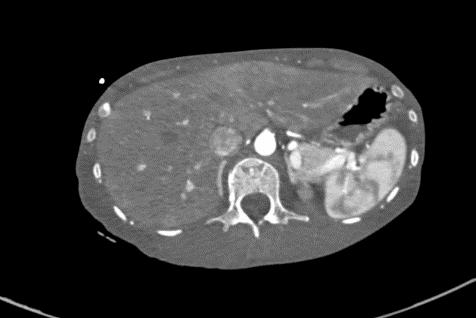

2021-4-29 CTPA:肺动脉干、左右肺动脉及其分支未见狭窄及明显充盈缺损。右肺、左肺下叶见斑片影、磨玻璃影及实变影。

2021-4-29全腹增强CT:腹盆腔散在积液,上腹腔少量积气,腹壁软组织积气,盆腔置管影。肝实质灌注不均,肝内淋巴瘀滞,提示肝功能损害。右侧见一支副肾动脉;左肾动脉提前分支。双侧附件区见多房囊状低密度影,可见环状强化,囊肿?卵泡?或其它?

患者青年女性,慢性病程;主要表现为腹胀、呼吸困难,术后出现意识障碍、II型呼吸衰竭。经呼吸机辅助呼吸、对症支持等治疗后,患者意识恢复但呼吸困难无明显改善;既往有有粉尘接触史。查体见患者极度消瘦、营养不良,双肺呼吸音粗,可闻及散在湿啰音。血气示II型呼吸衰竭、高碳酸血症,轻度贫血,低蛋白血症,电解质紊乱,炎症指标、肌酶、BNP升高,院外腹水检查示漏出液,未见肿瘤细胞;胸部CT:双肺斑片影,抗感染治疗后病灶吸收;腹部增强CT:双侧附件区分别混杂密度团块影,内见多发囊泡影;心脏彩超:右心稍大,重度肺动脉高压。